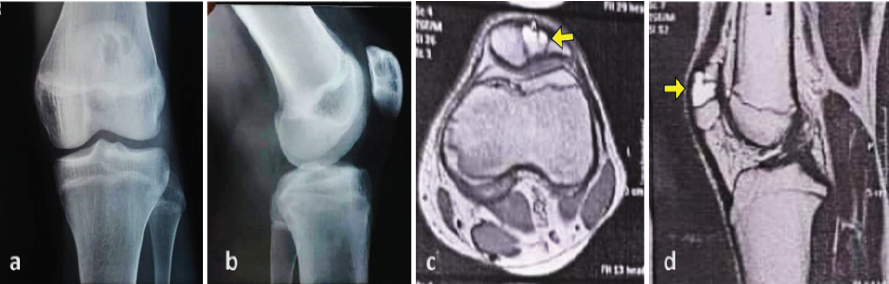

A 16-year-old male cricketer presented with a 2-month history of dull aching, anterior knee pain that had aggravated over the preceding 2 weeks. The pain was exacerbated by physical activities but did not restrict mobility. There was no history of trauma. Clinical examination revealed quadriceps muscle wasting with no obvious swelling or tenderness. The range of motion was preserved, while floating patella test and special tests for ligamentous injuries were negative. Plain radiographs of the left knee showed a well-defined lytic lesion along the superolateral aspect of the patella, with a narrow zone of transition and no perilesional sclerosis (Fig. 1). The joint space remained unaffected. Magnetic resonance imaging (MRI) revealed a 2.5 × 1.4 × 2.1 cm mild expansile patchy lesion with clear margins, and narrow zone of transition, hypointense on T1 and hyperintense on T2. Multiple fluid-fluid levels were observed on sagittal T2 sequences, leading to a pre-operative diagnosis of ABC of the patella (Fig. 1).

Figure 1: Imaging studies of the knee. (a and b) Anteroposterior and lateral radiographs demonstrate a well-defined osteolytic lesion within the patella. (c and d) Axial and sagittal T2-weighted magnetic resonance imaging sections reveal fluid-fluid levels within the lesion.